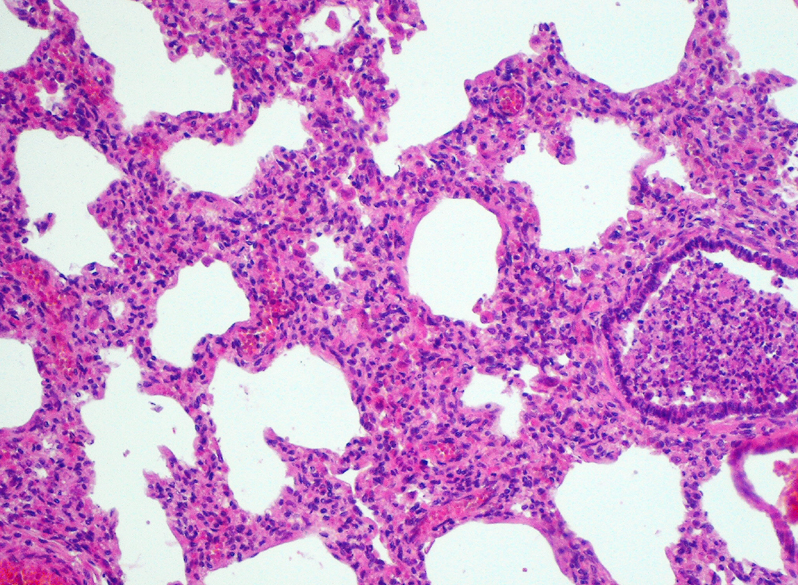

Slide:

Describe the appearance of the

Normal area and Inflamed area:

Bronchopneumonia

Bronchi filled by pus (inflammation start in bronchi, then involves other areas) (neutrophils, cellular debris).